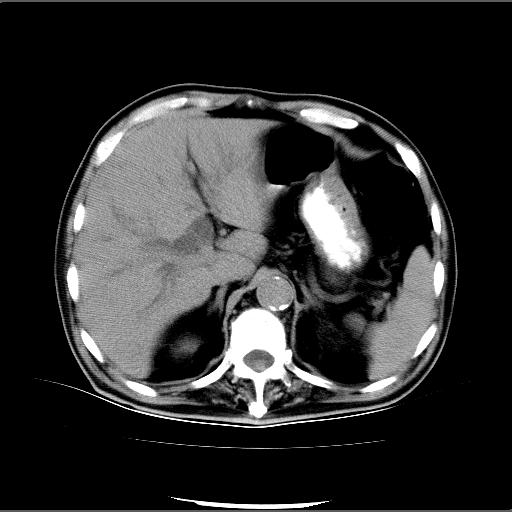

患者男82岁,黄染,发热10天,无腹痛。

1胆总管下端结石伴肝内外胆管扩张;2胆囊颈部结石伴胆囊积液

胆囊多发结石,胆囊积液;胆总管中下段结石,中上段扩张。

胆总管下段结石伴胆道系统扩张;胆囊炎伴胆囊结石.

1、胆总管壶腹部结石并胆总管、胆囊及肝内胆管扩张。2、胆囊多发结石。3、两下胸膜局限性增厚。4、胃体部大弯侧胃壁稍厚,建议:多量饮水后增强ct扫描除外占位性病变。

此病例有结果了:患者术后为:胆总管下段结石伴胆道系统扩张;胆囊炎伴胆囊结石。

各位战友分析的都很正确,是一个典型的病例。